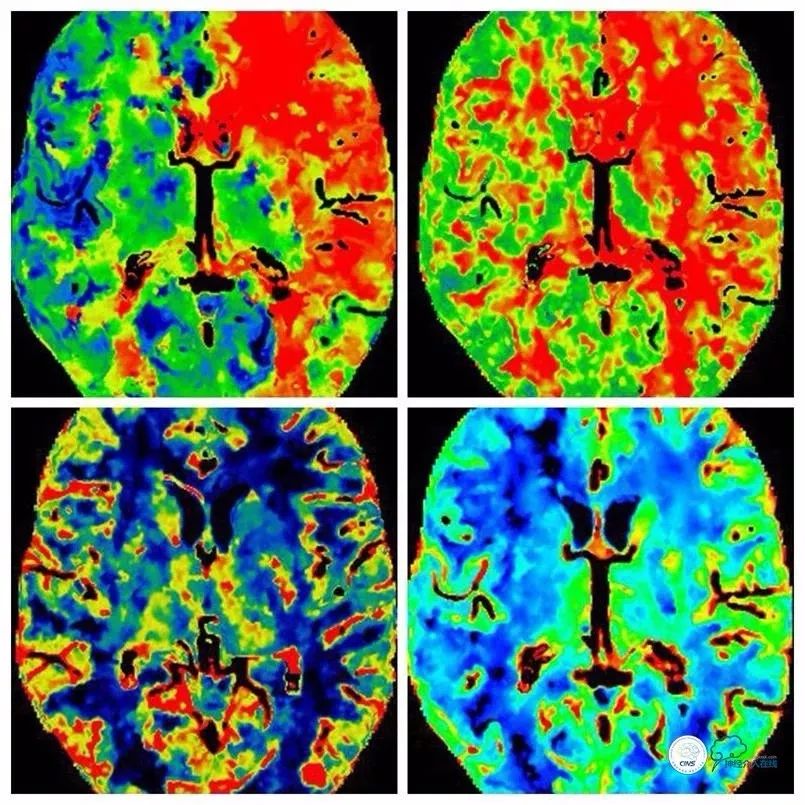

头颅CTP:左颈内动脉供血区低灌注(图3)。

图3

术前TCD:左颈内动脉颅内段峰值流速无法测出,探及鸥鸣样杂音,左大脑中动脉远端深度49mm处血流速27cm/s。相关区域主要由左大脑后动脉代偿供血。